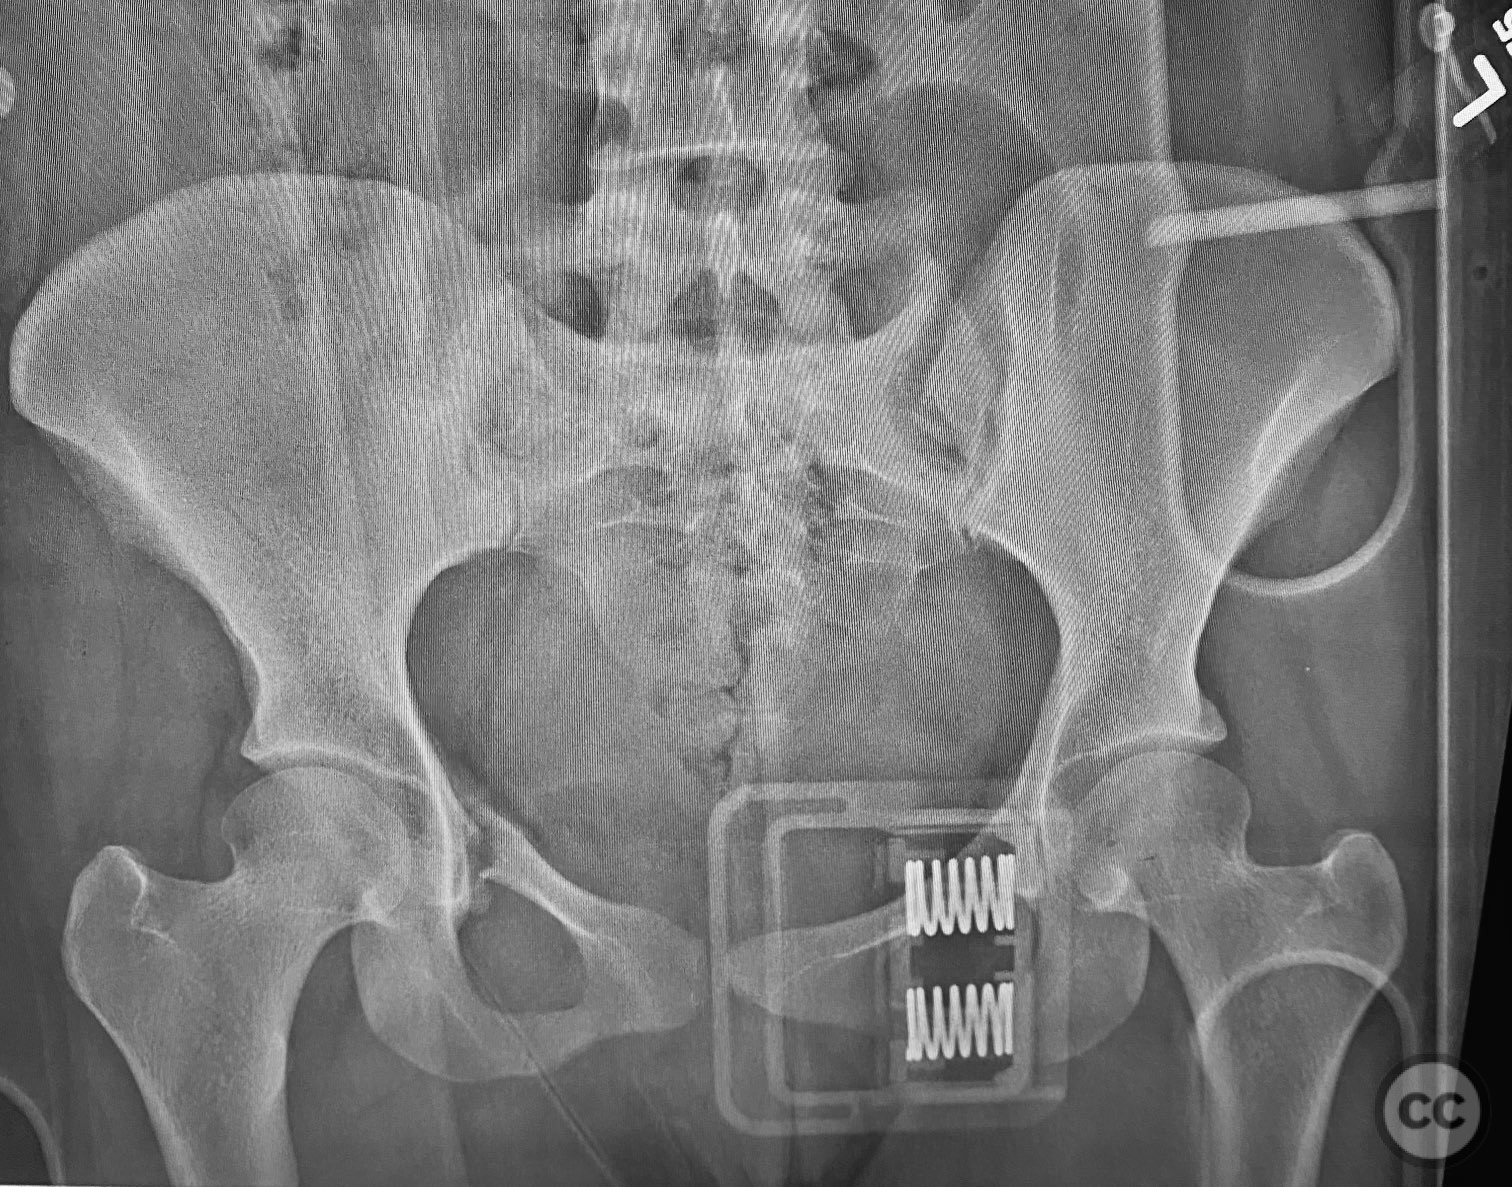

Clinical and radiological findings:  A young adult female sustained a high-energy pelvic injury following a motorcycle crash. She was hemodynamically stable on presentation, with normal neurovascular examination and no evidence of genitourinary, vaginal, or rectal injury. She reported pain localized to both anterior and posterior pelvic regions. Initial plain radiographs (with and without pelvic binder) demonstrated multiple anterior ring fractures and dislocations. The binder images obscured the full extent of injury. Further intraoperative fluoroscopic imaging (AP, inlet, and with lower extremities in "lotus" position) revealed bilateral sacroiliac (SI) joint disruptions (right greater than left), bilateral superior/inferior pubic ramus fractures (right greater than left), and symphyseal diastasis. Notably, the right pubic ramus demonstrated excessive curvature, complicating potential percutaneous screw fixation. AO/OTA classification: 61-C1.3 (bilateral complete disruption of the posterior arch with associated anterior ring injury). Young-Burgess classification: APC III.

Planning remarks:  The preoperative plan included open reduction and internal fixation (ORIF) of the displaced right pubic ramus fracture and symphyseal diastasis via an anterior approach, with acceptance of indirect closed reduction of the SI joints. Percutaneous trans-sacral screw fixation was planned for stabilization of the posterior pelvic ring. Due to the complex curvature of the right ramus, straight screw fixation was deemed unsuitable.

Intraoperative fluoroscopy with AP and inlet views, as well as dynamic positioning of the lower extremities, was critical in fully delineating the extent of injury, which had been underestimated on preoperative imaging due to binder application. The excessively curved morphology of the right pubic ramus precluded safe or effective straight screw fixation; therefore, ORIF with a contoured plate was performed using intrapelvic exposure for optimal fit and stability. Indirect closed reduction of the SI joints was accepted, followed by percutaneous trans-sacral screw fixation under fluoroscopic guidance. This case highlights the necessity of thorough intraoperative assessment for occult or underestimated injury patterns in complex pelvic trauma, particularly when initial imaging is performed with a pelvic binder in situ.

Orthopaedic implants used:   Pre-contoured anterior pelvic reconstruction plate; percutaneous trans-sacral cannulated screws